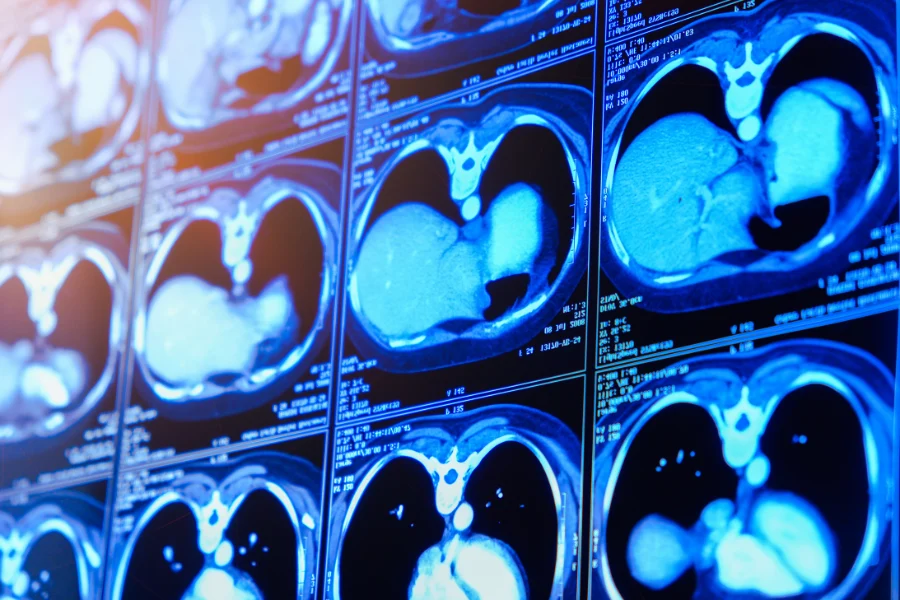

КТ брюшной полости (КТ ОБП) — один из самых информативных методов диагностики состояния внутренних органов. Это исследование позволяет врачам буквально «заглянуть» внутрь организма без хирургического вмешательства. На снимках чётко видны печень, почки, поджелудочная железа, селезёнка, желудок, кишечник, сосуды и лимфатические узлы. Особенно точным считается КТ брюшной полости с контрастом, которое помогает различить даже мельчайшие патологические изменения — от воспалительных процессов до опухолей на ранних стадиях.

Компьютерная томография (КТ) — это метод диагностики, основанный на применении рентгеновского излучения. Аппарат вращается вокруг тела и делает сотни послойных снимков, которые затем объединяются в трёхмерное изображение. Такой формат позволяет детально оценить состояние органов брюшной полости и выявить даже минимальные изменения в тканях и сосудах.

Контрастное вещество, вводимое внутривенно перед сканированием, значительно повышает диагностическую точность. Оно «подсвечивает» сосуды и структуры органов, делая изображение более чётким. Благодаря этому врач может отличить, например, доброкачественное образование от злокачественного, оценить кровоснабжение опухоли или наличие метастазов.